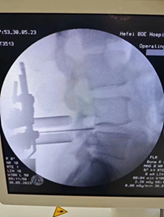

前有大血管,后有脊髓神经。中间夹着被肿瘤入侵的脊柱骨,稍有闪失非死即瘫。

面对脊柱损伤、术中出血、肿瘤复发三大风险,刘艺明带领团队凭借精湛实力,为患者开展了脊柱外科难度最高的手术之一,脊柱肿瘤整块切除术(En-block)。

完整切除了遭肿瘤侵犯的整个椎体,植入人工椎体。成功抢救脊髓,同时也降低了肿瘤复发的可能。